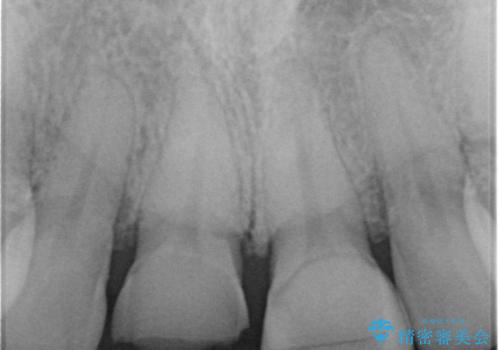

ラミネートべニアが取れた ジルコニアクラウンでの修復

- 前歯につけていたべニアが取れたとのことで来院された患者様です。

より脱離リスクの低いクラウンでの修復を行います。

取れていない方のべニアも周囲の歯と色調が合っていなかったため、一緒にやり替えました。

脱離リスクを抑えつつ、審美性も確保できたことで大変喜んでいただけました。